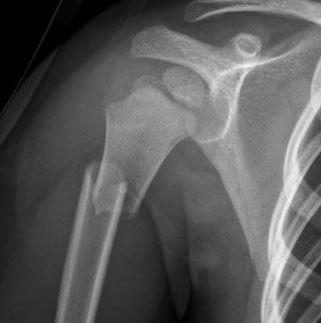

Chest and Abdominal X-ray:

- Bilateral pleural effusion;

- Perihepatic ascitic effusion;

- Displaced proximal diaphyseal fracture of the right humerus;

- Non-displaced distal diaphyseal fracture of the right radius;

- Non-displaced fracture of the right ischial tuberosity.

- Intramedullary metal fixation of the right humerus with brace (17/07).